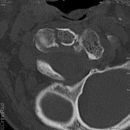

Sakroiliitis bei Bechterew